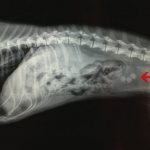

На приеме у ветеринарного врача дерматолога очень часто бывают собаки с отитами разной этиологии (происхождения). Для грамотного лечения необходим подробный анамнез жизни и болезни животного. Также, для постановки диагноза, врачу обязательно нужно проводить отоскопию

(осмотр слухового прохода с помощью отоскопа) ушных раковин и

цитологию

(микроскопическое исследование) ушного содержимого. Возможно, при оценке состояния животного на приеме, потребуются дополнительные методы исследования, о котором сообщат владельцу.

Факторы для возникновения отита:

предрасполагающие факторы, первичные причины, вторичные причины. Поговорим более подробно о каждом факторе.

Предрасполагающие факторы – висячие уши; стенозирование (сужение) ушной раковины; избыточный рост волос в ушных каналах; интенсивное плавание; избыточная выработка серы; ятрогенные (человеческие) факторы, такие как, частое мытье и чистка ушей, чрезмерный тримминг.

Первичные причины отита у собак – аллергия, атопия, пищевая аллергия, паразиты, эндокринные патологии, церуминозная аденома, церуминозная аденокарценома, гиперадренокортицизм, катаболические болезни, иммуносупрессия, инородные тела, назофарингиальные полипы, неоплазия, идиопатический отит коккер-спаниелей, пузырчатка, волчанка, буллезный пемфигоид, аденит сальных желез, чума плотоядных.

Вторичные причины возникновения отита у собак – бактериальные (стафилококки, стрептококки, энтерококки, синегнойная палочка, протей, кишечная палочка, клебсиелла и т.д.), дрожжевые (малассезия, кандида).